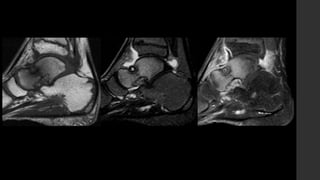

Tumor de Células Gigantes.

•También conocidos como osteoclastomas.

•Son tumores óseos relativamente comunes,

usualmente benignos que nacen de la metáfisis y se

extienden hacia la epífisis de los huesos largos.

•Representan 18 – 23% de los tumores benignos óseos

y 4 – 9.5% de todos los tumores primarios óseos.

• Se presentan una vez que los núcleos de osificación ya cerraron, por lo que se

observan en la etapa adulta temprana (80% de los casos se presentan entre los 20 y

50 años con pico de incidencia entre los 20 y 30 años).

• Hay discreto predominio por las mujeres, sin embargo la transformación maligna es

más común en hombres (M:F – 3:1).

• No tienen presentación clínica específica, sin embargo presenta dolor óseo insidioso,

masa de tejidos blandos, compresión de estructuras adyacentes o, de forma aguda,

con fractura patológica.